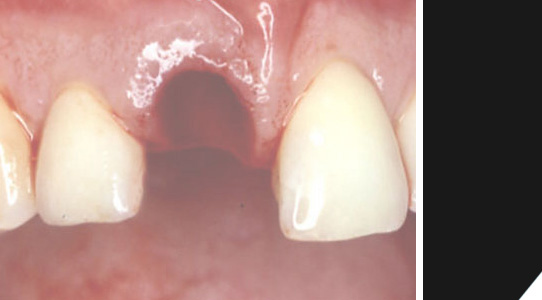

Der Restzahn wurde entfernt.